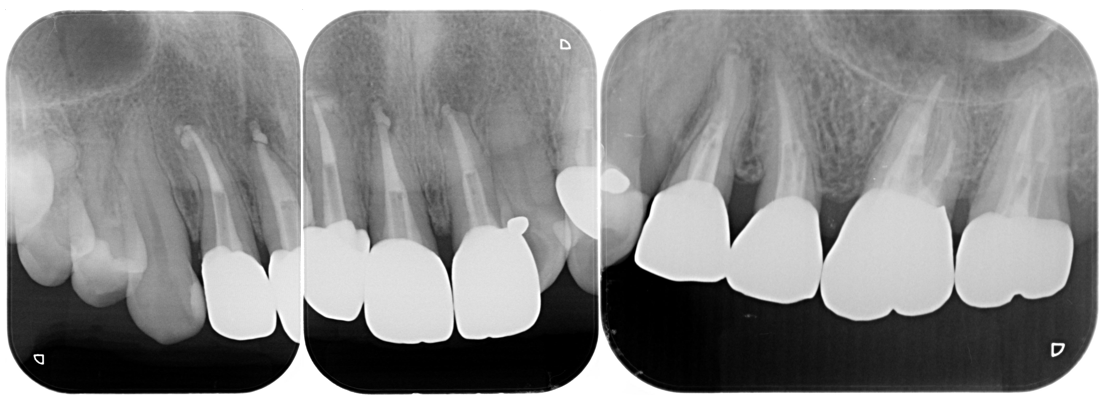

症例3

| 医院の診断 | 虫歯の再発、慢性根尖性歯周炎、炎症による歯髄狭窄、歯根の湾曲、人為的破折ファイルの存在 |

| ここがこだわりのポイント!☝ |

歯髄狭窄+歯根湾曲+破折したファイルの存在が複合した歯でした。 ラバーダム防湿とマイクロスコープを使用して丁寧に治療を行いました。 再根管治療のため、殺菌性があり歯を補強することのできる根管充填材料を使用しています。 |